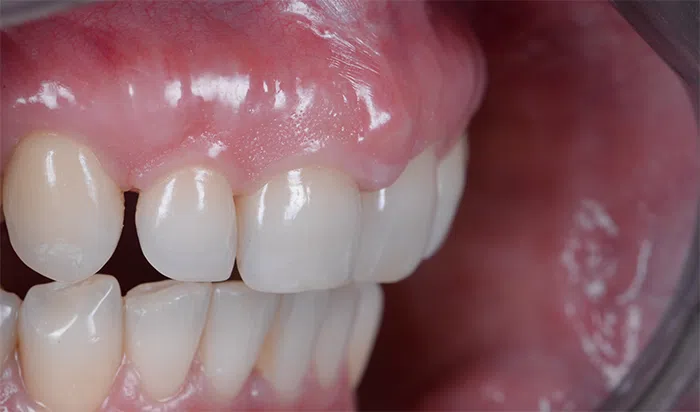

După

Caz de estetică dentară – Fațete ceramică presată E-Max

Provocarea acestui caz a fost în prepararea minim invazivă a dinților centrali rotați și a obține o formă și o culoare cât mai naturală, pacienta dorind un caz de estetică dentară ce să nu fie observabil.

Pacienta a beneficiat de corecție gingivala cu laser pentru uniformizarea asimetriilor gingivale, tratamente endodontice de canal sub microscop, obturațiile vechi (plombe) schimbate cu materiale de compozit cu particule nanoceramice, și fațete dentare din ceramică presată E-Max.

Termen de finalizare 2 săptămâni de la amprentarea finală.